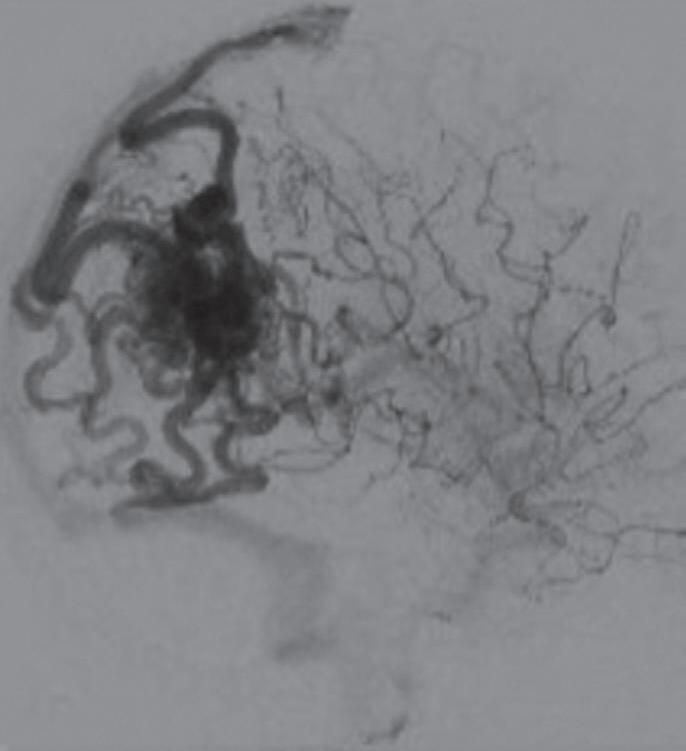

Com relação ao fluxo no interior do nidus, alguns autores classificam-nas em alto fluxo (Fig. 1-8) e baixo fluxo (Fig. 1-9). São consideradas de alto fluxo aquelas em que a opacificação após injeção de contraste ocorre apenas na malformação, em contrapartida, nas de baixo fluxo, ocorre opacificação da MAV e de outras artérias normais do mesmo território vascular. Exemplificando as lesões de alto fluxo temos as malformações arteriais, as malformações arteriovenosas e as fístulas arteriovenosas, enquanto as lesões de baixo fluxo são representadas pelas malformações venosas, linfáticas e capilares.25

Fig. 1-15. RNM encéfalo T1 (a) sagital sem contraste e (b) axial com contraste demonstrando MAV grau 3, parcialmente embolizada, localizada no giro temporal superior e lobo parietal direito. (c) Arteriografia cerebral em perfil, demonstrando a irrigação pelos ramos da artéria cerebral média e posterior, com drenagem superficial nas veias de Labbé até o seio sigmoide, e o complexo de Trolard no seio sagital superior. O nidus da MAV está demonstrado pelas setas azuis grandes e a drenagem venosa pelas pontas de setas.